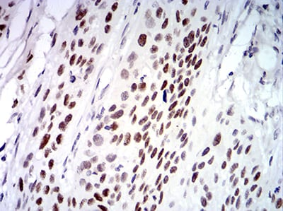

IHC    1/200 - 1/1000